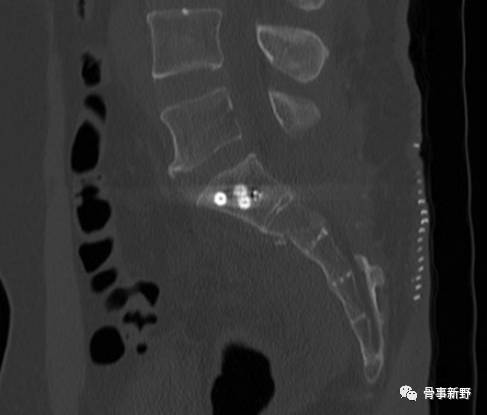

S2 骶髂螺钉的骨性通道常较S1小,因而使得 S2骶髂螺钉的置人风险相对更高。难度大,一般在S1 椎体发育畸形或骨质破坏时采用。

Osterhoff G等(2011)将S2骶髂螺钉的进钉 点 确定 在 S2椎 体上下终板平分面上,并位于该面与椎体后缘交点背侧几毫米 。Moed BR等(2006)则将进钉点确定在标准骶骨侧位像上 S2椎体上下终板 、椎体前后缘所围成区域的中央 (即 S2 椎 体中点 )。